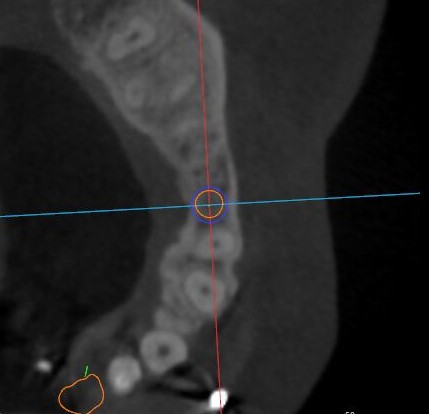

觀察患者CT,可看出患者有上頜竇粘膜囊腫,粘膜囊腫為竇內(nèi)腺體阻塞所致,視情況可有手術(shù)摘除和不予處理兩種方法,此次患者拒絕手術(shù)摘除,故需規(guī)避上頜竇位置。

冠狀面視圖

矢狀面視圖

軸狀面視圖

三維視圖

根據(jù)患者CT顯示,使用種植導(dǎo)航軟件設(shè)術(shù)前手術(shù)方案??紤]到患者拒絕手術(shù)摘除上頜竇囊腫等因素,此次手術(shù)選用了Straumann骨水平4.10*8.0mm的植體,植體末端位點(diǎn)設(shè)計(jì)距上頜竇底壁2mm處的同時(shí)兼顧種植方向和修復(fù)間隙,來(lái)達(dá)到理想的效果。